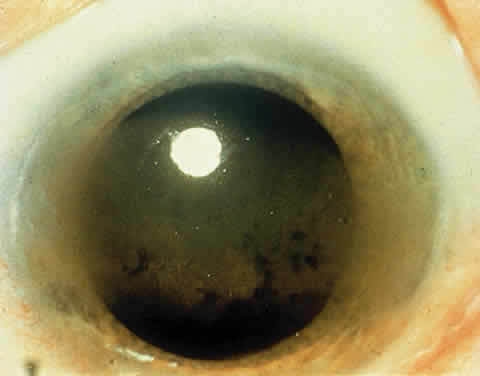

OCULAR FINDINGS. The outstanding clinical feature common to all three phenotypes is the corneal and conjunctival cystine crystal deposition (Figs. 3 and 4). Photophobia is often the only presenting visual symptom; this may be incapacitating and associated with blepharospasm.

Corneal deposits appear as a layer of homogeneously distributed, fusiform or needle-shaped, iridescent crystals situated in the stroma beneath the epithelium. In the infantile form, anterior crystal deposition begins early in life (between 6 and 15 months of age) and proceeds posteriorly as the patient ages; deposition advances more rapidly in the periphery. The anterior location of the crystals may be associated with recurrent erosions.33 The depth of the stromal deposition and the density of crystals is always greater peripherally than centrally. More and larger crystals occur in the superficial stroma. No visual impairment occurs at this early stage. By the age of 7 years, most patients have crystals, either within or on the endothelial surface34,35; markedly decreased corneal sensitivity is also present.36 The spherical contrast sensitivity function is significantly lower in infantile cystinosis than in age-matched controls.37

The conjunctiva has a ground-glass appearance. Polychromatic, polymorphic, rectangular, or rhomboidal crystals can be seen with the biomicroscope.

The uvea contains an abundance of polymorphous crystals. Clinically, these can be seen as glistening dots on the surface of the iris. Thickened iris stroma and posterior synechiae may occur; pupillary block glaucoma38 also has been reported. The entire uvea has polymorphic crystal deposition, most heavily in the choroid. The sclera also has crystal deposition.